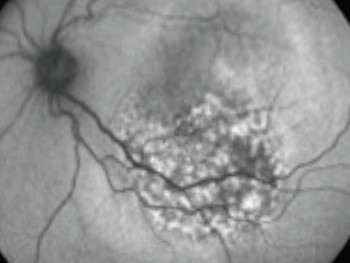

A Angiografia Fluoresceínica (AF), ou Angiofluoresceinografia, é um exame de grande importância no estudo das doenças que atingem a retina, coróide e nervo óptico. Doenças como Retinopatia Diabética, Degeneração Macular Relacionada à Idade (DMRI), Degenerações retininas hereditárias, Doenças oclusivas vasculares, entre outras, têm indicação para realizar esse exame, que apesar do nome complicado, é relativamente simples em sua realização, porém necessita grande experiência na área de retina e vítreo para a sua interpretação.

O exame é baseado na realização de fotografias do fundo de olho do paciente, após a injeção de um contraste, em uma veia do antebraço ou dorso da mão. As principais reações adversas que podem ocorrer, que não são freqüentes, são dor local se houver extravasamento do contraste, náuseas (5%) e vômitos (0.3%), mais comuns em jovens. Raras são reações alérgicas como coceira, vermelhidão local, edema de laringe, broncoespasmo, tromboflebite. São relatados casos raros de choque anafilático, infarto e até morte (0.0004%). O contraste é eliminado pelo organismo em torno de 24 horas, pelo fígado e rins, alterando a coloração da urina e pele nesse período. Deve –se evitar exposição solar por um período de 48 horas, para não haver reações urticariformes. O exame está contra-indicado em portadores de insuficiência renal, hepática e cardíaca não controlados, e em pacientes epilépticos. Após dilatação das pupilas com colírios, é feito o posicionamento do paciente no aparelho e injetado o contraste em cinco segundos. São realizados filmes e fotos seqüenciais são tiradas pelo oftalmologista, durando o exame de 5 a 10 minutos, conforme a doença estudada.